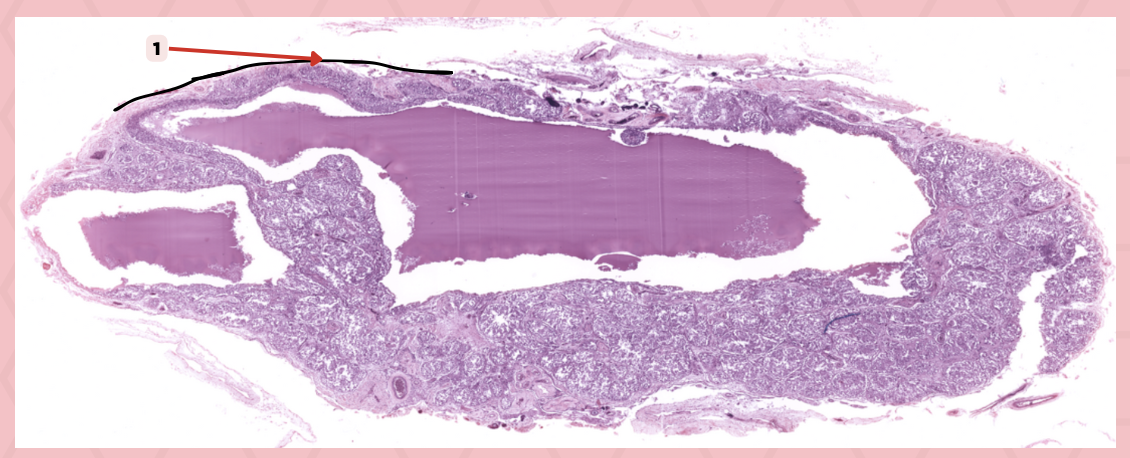

Thyroid-Parathyroid

Identify the specimen.

Thyroid Gland

Identify the structure labeled as 1.

Capsule

Identify the structure labeled as 2 and 4.

Parathyroid Gland

Identify the structure labeled as 3.